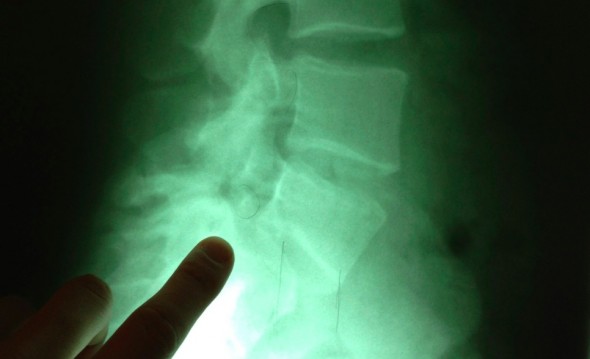

- Doc: Hey, so here are your x-rays. Um, have you ever had a serious fall in the past? Like, 10 years ago or so?

- Doc: Well, let’s take a look at your x-ray here (see photo above). Look at your L5 Vertebrae – it’s supposed to line up with the rest of them…it’s off by quite a bit.

- Me: Wait, that’s supposed to line up with the rest of them? Ruh roh…